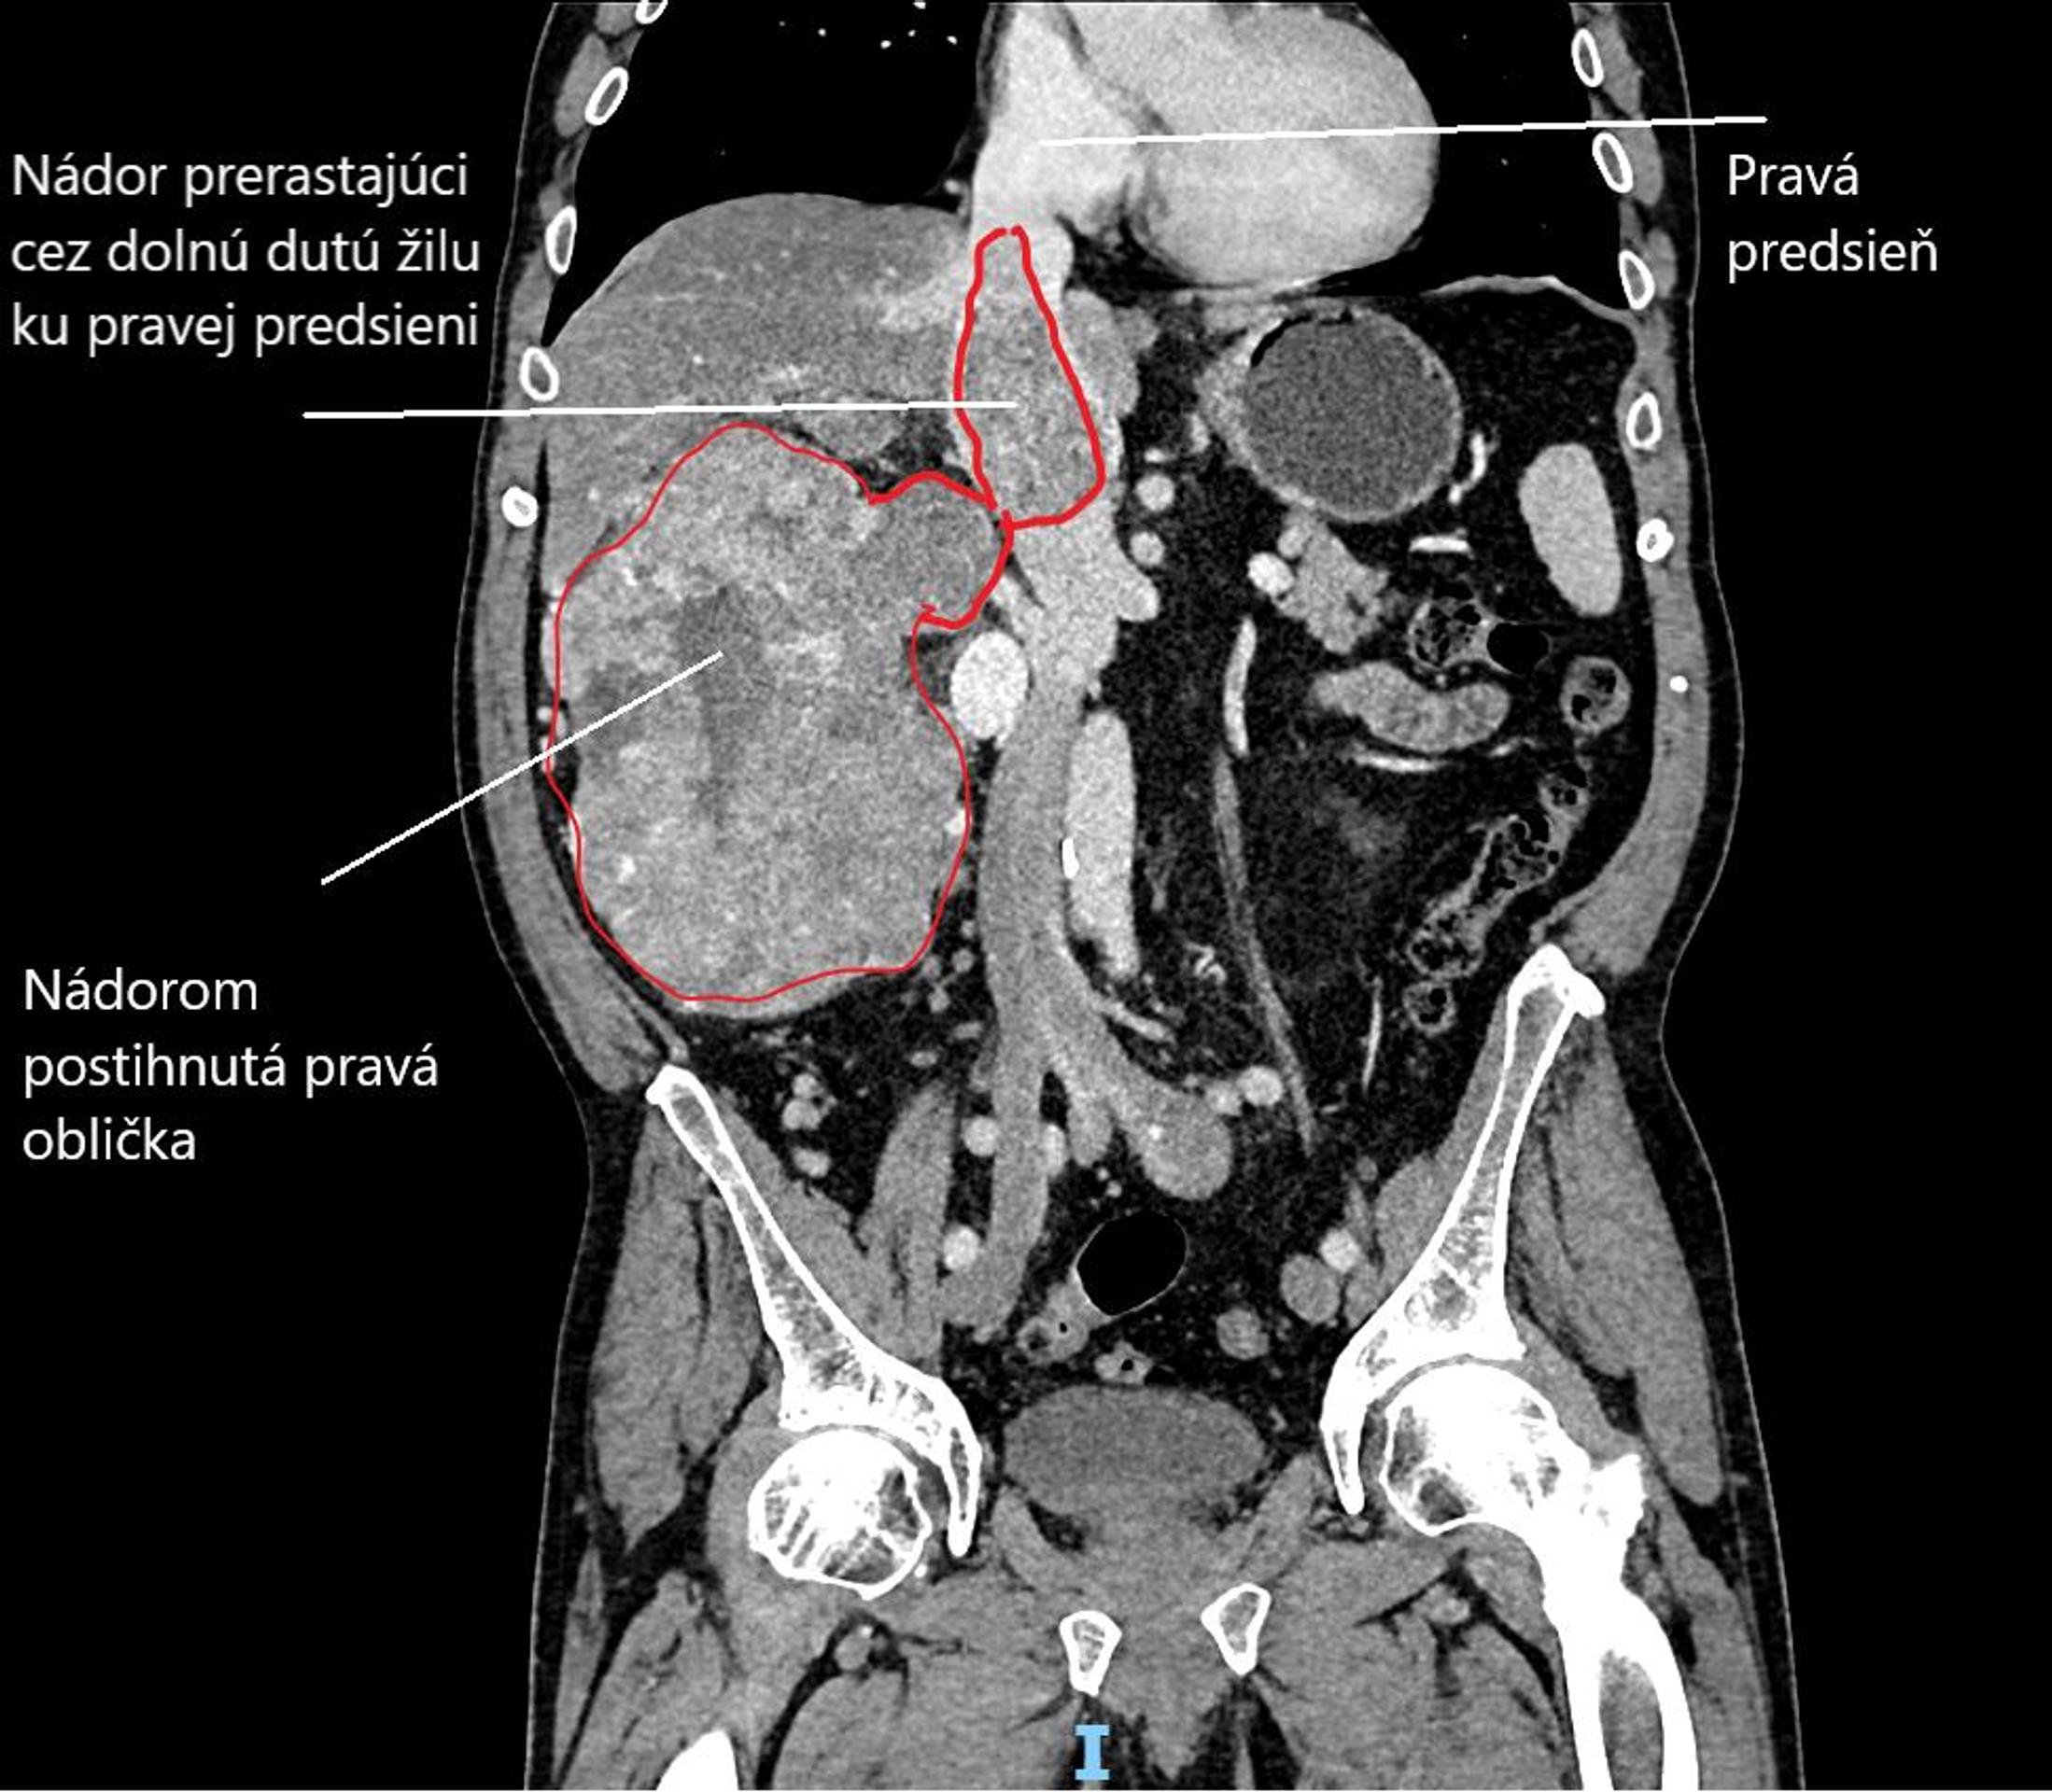

Operácia nádor.

Zdroj: Facebook/Fakultná nemocnica s poliklinikou F. D. Roosevelta Banská Bystrica